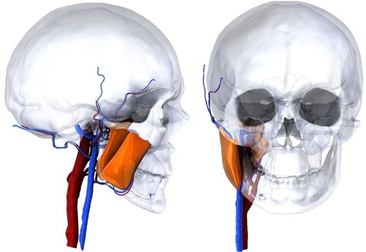

- Биоинженерия – проекты, направленные на улучшение медицинских технологий и методов лечения (расчет подвижности сосудов, прочности протезов);